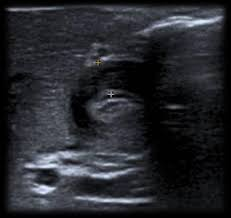

Caracterizada por un engrosamiento anormal del músculo pilórico, lo que lleva a una obstrucción de la salida gástrica. Esta condición es una causa común de vómitos no biliosos en lactantes y generalmente se presenta entre las 2 y 12 semanas de vida.

El diagnóstico se realiza principalmente mediante ecografía, que muestra un alargamiento constante y un engrosamiento de la pared del píloro, con una longitud del canal pilórico superior a 18 mm y un grosor muscular de al menos 4 mm.

Ejemplos de estenosis pilorica hipertrofica infantil.